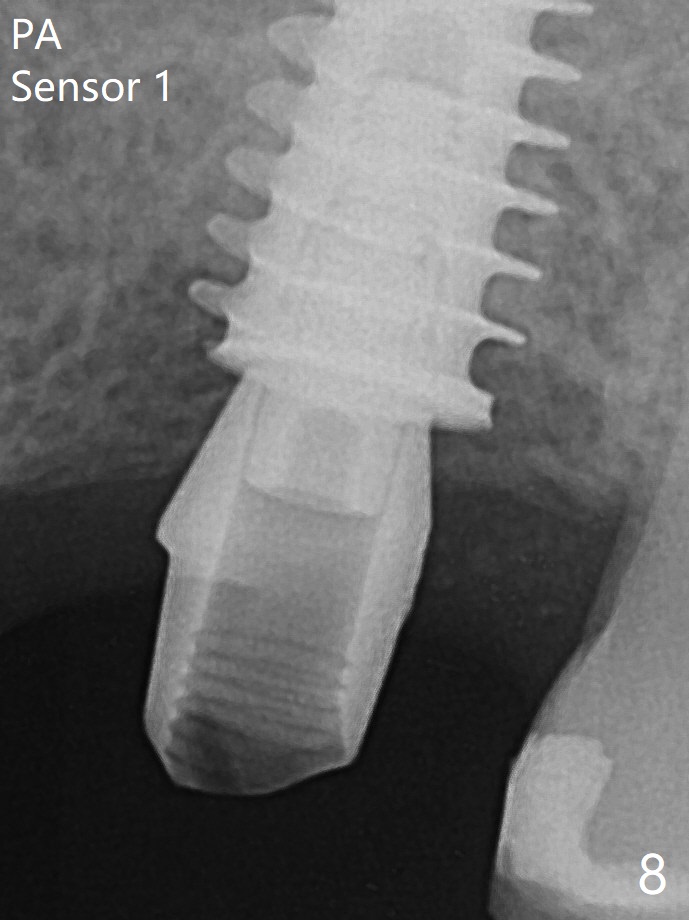

After extraction of the tooth #14 with palatal swelling (Fig.1 *), the septum (S in Fig.2) is found to be thin. Sequential osteotomy quickly deviates to the palatal socket. In spite of using Lindamann bur to remove the bone from the buccal portion of the osteotomy, the apical end of a 5x9 mm dummy implant slides into the palatal socket with the coronal end placed as buccal as possible for restoration (Fig.2 (poor trajectory)). Further use of Lindamann bur for buccal bone removal is not feasible, since the buccoapical portion of the osteotomy starts to be perforated with apparently intact sinus membrane. With insertion of Vanilla graft for sinus lift through the buccoapical portion of the osteotomy mentioned above, a 6x11 mm implant is placed with the same trajectory (Fig.2, <40 Ncm). With placement of a 6.5x4(3) mm abutment (off angle) and of Vanilla graft in the remaining sockets (Fig.2 *), periodontal dressing is applied. When the dressing is dislodged for the 2nd time (12 days postop with healing socket), an angled abutment 5x15 degree, 3 mm cuff, is placed and a provisional is fabricated. There is no sign of sinus infection. The provisional and angled abutment become loose without sinus infection 2 months postop. A 5.5x3 mm healing abutment is placed with light tenderness. If this case turns to be failure, do not stick an immediate implant from potentially infected socket into the sinus in the future. The socket appears to heal 11 months postop (Fig.4). Later a 5x4(3) mm abutment is placed for final restoration. The palatal margin is low. The abutment screw is loose <2 months post cementation, probably due to deep placement and poor trajectory (buccal). It becomes loose again 4 months later. Prior to retightening, a 6 mm profile drill is used. BW shows no bony interference (Fig.5 (opposing tooth occlusal wear; bruxism)), while PA shows the buccal bone, suggesting poor trajectory. The abutment is loose for the 3rd time 17 months post cementation. When the crown/abutment is removed, the hex is worn. After proximal reduction, the crown/abutment feels to be unable to be re-seated. When the crown is sectioned, the abutment itself is incompletely seated (Fig.7,8). The mesial crest appears to interfere with seating (Fig.8). When the 5.2x3 mm dummy abutment is seated, the buccal margin is subgingival, while the palatal one supragingival, suggesting the buccally tilted implant (guided surgery essential). A 4.5x4(4) mm pair abutment seems to be seated completely (Fig.9). The hex of the 5x4(3) mm abutment is worn, but the abutment seems to be able to be seated completely (Fig.11), although not so crisply (easily) as the unworn one clinically. Return to Upper Molar Immediate Implant, Prevent Molar Periimplantitis (Protocols, Table), Armaments Screw Xin Wei, DDS, PhD, MS 1st edition 06/26/2018, last revision 12/20/2020